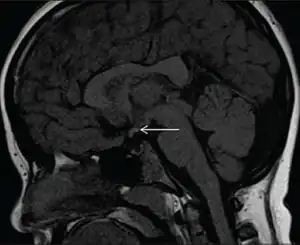

| Diagnostic method | MRI scan |

The diagnosis is confirmed through MRI.[2]